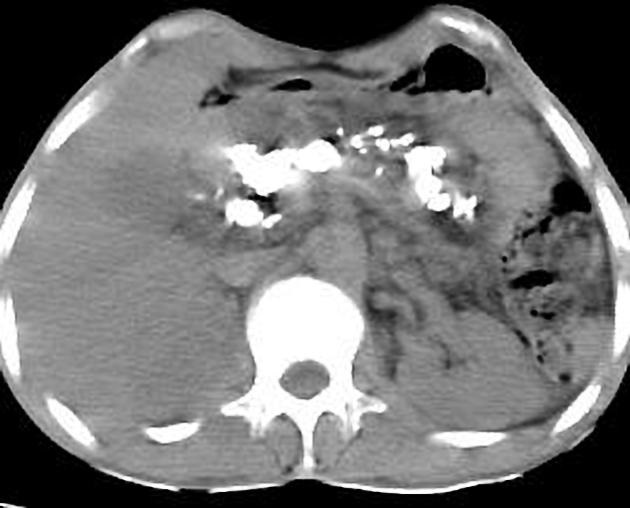

Pancreas volumineuse a

isodense, , bord irregulier .avec des calcifications

nodulaires ou multiforme tres hyperdense dissemine

intra parenchymateuse du pancreas . Image

radiologique TDM d'une pancreatite chronique

primitive en coupe axiale . |